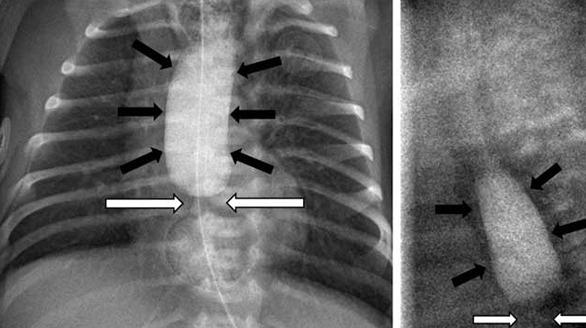

Paediatric Bronchoscopy (Foreign Body Removal)

Kids can accidentally inhale any object into their windpipe, which can lead to partial or complete blockage of airways. Young children especially between the age of 6 months till 3 years have the habit of putting objects into their mouth, including non-food items. Children can inhale pieces of peanut, almond, cashew nut, supari and any other dry fruit. Also, they can inhale objects which include plastic as well as metal such as ornaments, small toys/parts of toys (whistle), marble balls etc. This can lead to difficulty in breathing and even death of the child if not removed by emergency bronchoscopy.

We also carry out diagnostic newborn as well as pediatric bronchoscopy. It helps us in diagnosing problems like :

- Congenital Tracheomalacia

- H-Type Tracheoesophageal Fistula

- Laryngo-tracheal Clefts